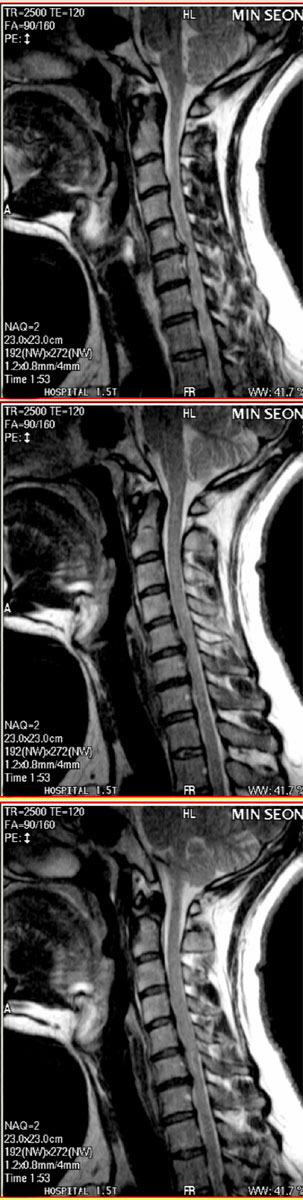

ܹ ũmri ¥ Ϸ ǥغ ϰ ڲ ġر ϰ ۼϽ Դϴ. no 3041 date 2008-04-15 10:20:20 hits 777 name Ȩ (@) IP: 219.249.201.116 - mri µ- ũ Ϸ ϰ ؽ ó Ǿ ϰ Դϴ. ڸ ũ Ͽ ȱ ȱ ڸ ؽ 1 ° ϴٰ Ŀ İ Դϴ. ᱹ ġر ġ Դϴ. ֹǰ (ֹȣ : 347c53bc2c12 / ī,ͳݹŷ ιȣ : 30006102 -- ۼϽ ȿ Դϴ.-- 523 MRI Դϴ no 3028 date 2008-04-10 16:00:01 hits 634 name μ* (nse3004@hotmail.com) IP: 123.214.2.188 ı .. Įִ̲µ , ʹ ϰ, ǿ ϰ ʰ... ǻ Բ ص ״δ.. ݿϿĿ MRI ϴ, ѻȲ̶ ٷ ڰ ؼ յڰ ħ ϰ Խϴ... Ǵ ٽ ۵ǰ غ ϰ ִµ, û ȴ ȭ Խϴ. ʹ µ.... ؾұ... Żϱ .... 10е ȰɷȽϴ..... Գ ߰ 2,3 ϱ ϳѰ .. ׳ ̸, ǻҶ, Ҷ ڼ ˷ֽð MRI Ͻø鼭 ֽŰ մϴ.. ׳ ߷ µ Ż Բ, Ծϴ.. ̹ȸ ڴ½ð ߿伺, ̳ ġῡ Ǿϴ. ¼ ̽ð شθ ð ߴµ, ɲ ḱ , ڿġḦ Ҽִ ȸ ּż ϴ... ȫ ϸ鼭 ڽϴ... P.S Լ س, ̺ ٽ ؾϴ 찡 ҽϴ. ũ Ͻ е ԿʹҾ Ʈ ϴ° ȿΰ ϴ. ƮĿ ٽϴ ܵ... --- 2 ۼֽ ҰԴϴ.--- ũ ... no 3153 date 2008-06-06 01:10:42 hits 439 name μ* (nse3004@hanmail.net) IP: 123.214.2.156 ½ 2 ȳ... 4 ߺϰ .... ¥(4ũ ΰ Ƴ) Ϸ Լϰ 10еȵǼ , ϰ....2ָ ȸ纹ؼ ݱ ٴϰ ֽϴ.... 2 ϸ鼭 ҽϴ... ǥغ ΰ ϴ. Ȯ 2ΰ, 61ϳ ߽ϴ...^^ ƽ? úҶ Ӹ... (ũ ִ ٴ ÷ Դϴ...) ġȰ ϴ.. ؾ߰... ٽñ 帮... âϽñ ϴ...ȳ.. * : ֽ ȸ̽Ű? ɰϰ ϰ ֽϴ. ܹ ȯڴ ȸ ؾ ϴ? 2009-11-26 19:51:54 * : ũ ִٸ ̵ Դϴ. Ի ҽϴ. Ŀ ȭ帮ڽϴ. 2009-11-26 20:19:57 Ȩ : * 㼱 ȸ Ӹƴϰ Ե ʴϴ. ȸ Ƿ ַ Ͻð ɰϰ ϴºе鲲 Ȯ ȿ ȸ Ϻη ϱ մϴ. 2009-12-01 00:38:12 Ȩ : ȸԸ ȯڵ ϴ° ƴϰ 迵ռ ؼڻ ̺е鵵 ȯ ص帳ϴ. 2009-12-01 00:39:28 ȫ* : ϱ ǽ ȿ . *Ժ ũ Ƣ ° ʾҴµ ߾. ־. ũ ȿ ? 2009-12-20 11:37:22 Ȩ: ȫ* Ŀ ִ ũ ־ Դϴ. Ŀ ̳ ϴ. ȸ ûϼ. ū 븦 ϼŵ ϴ. 2009-12-20 14:19:44 ڱ*: ΰ ؾ Ѵٰ ̳ ϰ ֽϴ 2010-01-30 20:57:07 Ȩ : ڱ* ؾ ° ñմϴ. ȯ 10 8~9 ǥغε ġ DZ մϴ. ؼ غ 2010-02-06 14:36:39 |